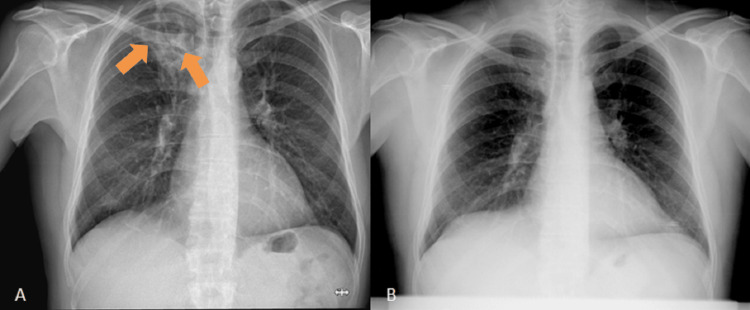

A chest radiography was performed, documenting heterogeneous hypertransparency with rounded contours and hypotransparent areas at the apex of the right lung. In comparison to a chest radiography taken 10 years earlier, the hypertransparency was de novo (Figure 1).

Figure 1. Images of the chest radiographs.

(A) Chest radiography taken on the day of admission to the emergency department, showing heterogeneous rounded hypertransparency of important dimensions at the apex of the right lung (orange arrows). (B) Chest radiography performed 10 years before, showing no abnormalities